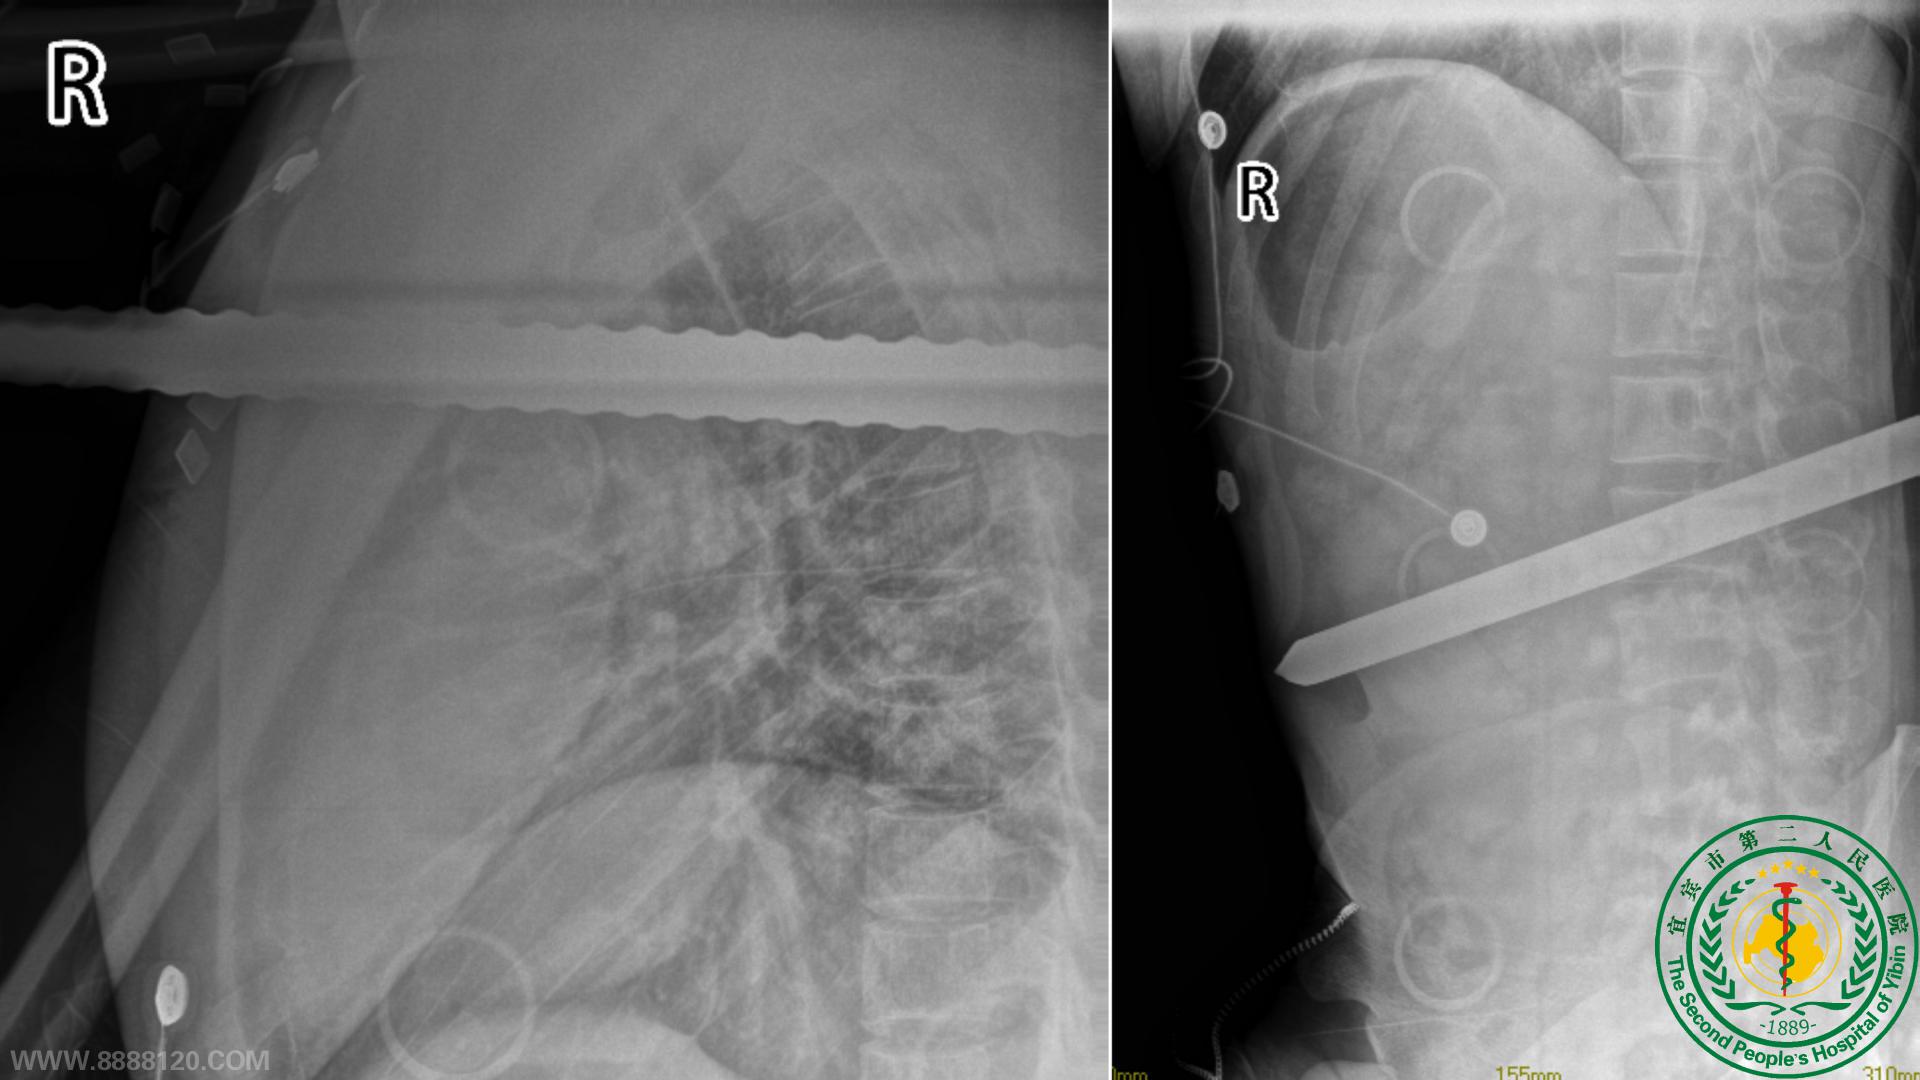

多学科联合协作,民工兄弟转危为安20905

宜宾市第二人民医院 图文